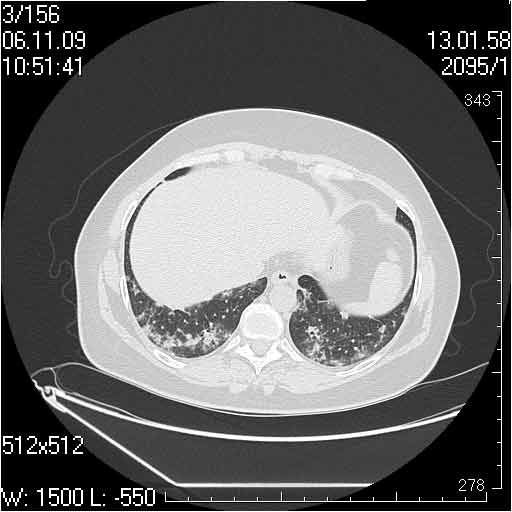

Случай №1

Женщина 50 лет.

Случай 1: изменения характерны для интерстициальной пневмонии (IIP/UIP idiopathic interstitial pneumonia/usual interstitial pneumonia); говорить о конкретной форме без открытой биопсии затруднительно.